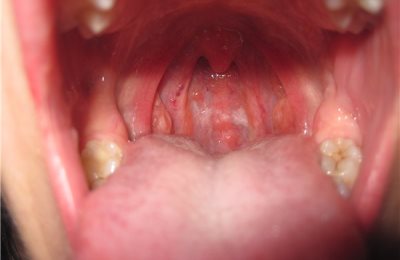

Лакунарная – самая тяжелая из банальных форм. Все миндалины покрыты налетом, лакуны заполнены желтовато-белым налетом, также наблюдаются боли при глотании, лихорадка и симптомы интоксикации, в том числе ощущение «кома в горле».

Ангины могут протекать с осложнениями, такими как паратонзиллит, пара- и ретрофарингеальные абсцессы.

Паратонзиллит – это воспаление околоминдаликовой клетчатки, проявляющееся в сильном повышении температуры до 39-40°С, невозможности приема пищи и сглатывания слюны из-за очень сильной боли, «кома в горле», удушья;  также характерен тризм – симптом, при котором человек не может полностью открыть рот из-за тонического спазма жевательной мускулатуры. В полости рта в проекции миндалины выявляется крупное выбухание.